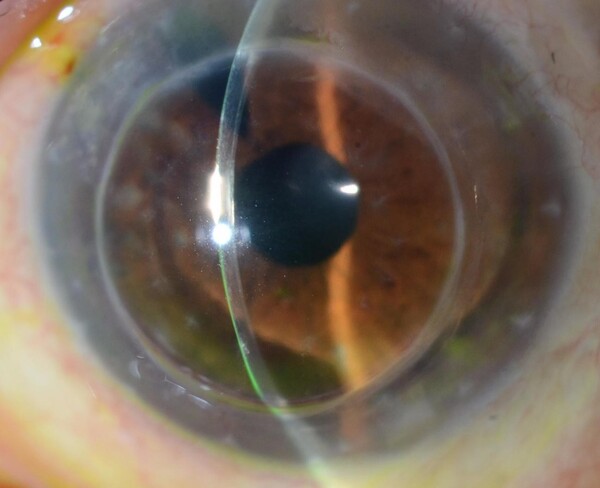

Edema Corneal

DEFINICIÓN

Cuando se pierde un número crítico de estas células endoteliales, el endotelio como un todo empieza a ser incapaz de mantener deshidratada la córnea y empieza a haber edema (líquido) en el espesor de la córnea. Al llenarse el estroma corneal de líquido, la córnea pierde transparencia. Al comienzo de la enfermedad endotelial, el edema suele ser mayor por la mañana, dando visión borrosa que dura alguna/s hora/s y luego mejora con el correr del día. A medida que empora la función endotelial, el edema se hace cada vez mayor, y proporcionalmente progresa la opacidad corneal.

Las enfermedades más comunes que generan edema corneal son: la queratopatía bullosa, donde el daño endotelial está asociado a cirugías oculares previas; la distrofia de Fuchs, donde hay una predisposición genética a una perdida acelerada de células endoteliales; el agotamiento endotelial de trasplantes penetrantes (de espesor corneal completo) previos.